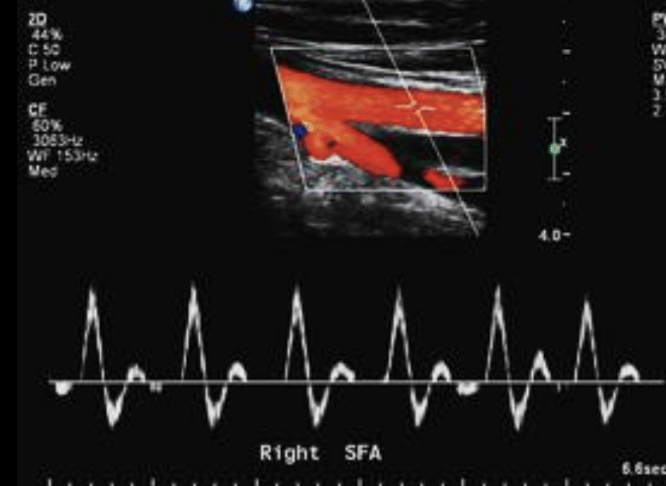

¿Onda anormal o trifásica?

Anormal